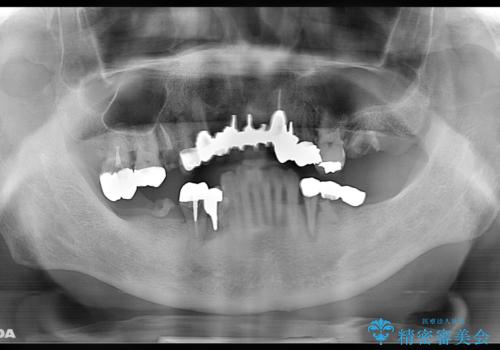

- お孫さんに口臭を指摘されたことで治療を決断し、来院されました。

歯周病、虫歯、合わない被せ物がニオイの原因となっていたため、そのすべてを治療することになりました。

まずは歯周病の治療と抜くしかない歯を抜き、インプラント治療とセラミック治療を行いました。